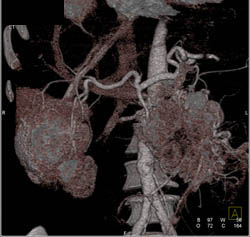

Islet Cell Tumor With Liver Metastases